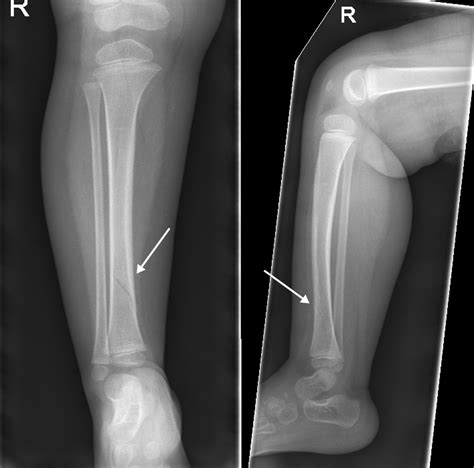

Medical X-ray of a leg

The tibia, or shinbone, runs from your knee down to your ankle. It is a critical component of the musculoskeletal system, acting as a primary weight-bearing structure. Fractures in this area can range from stress fractures—which are tiny, hairline cracks—to complete breaks where the bone snaps into two or more pieces. Most instances occur due to high-energy trauma, such as car accidents, falls from significant heights, or contact sports, although repetitive stress can also lead to fractures over time.

3. Seek medical imaging: Doctors will almost always order an X-ray to determine the exact location and severity of the break.

When you arrive at a clinic or emergency department, the medical team will evaluate your Tibia Fracture Symptoms through a series of diagnostic steps. They will perform a physical examination to check for pulses in the foot and sensory function in the lower leg. Following this, imaging is mandatory. X-rays provide a clear image of the fracture lines and displacement. In more complex scenarios, such as injuries involving the knee or ankle joint, a CT scan may be requested to gain a three-dimensional view of the bone structure.